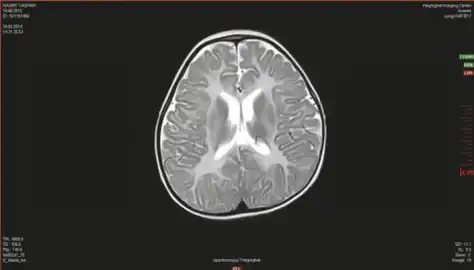

Canavan’s disease demonstrates bilateral symmetric T2 white matter hyperintensity including involvement of the subcortical arcuate fibers